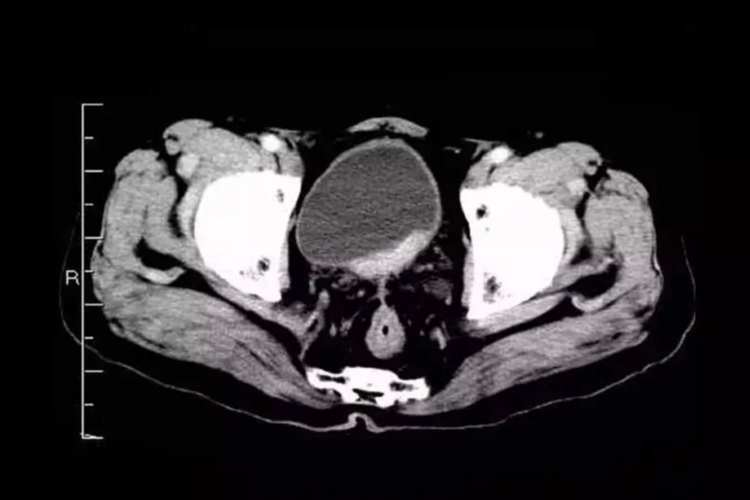

盆部CT检查

盆腔扫描范围从髂嵴至坐骨结节下2cm。阴茎、阴囊病变,扫描范围应包括外阴下界。

适用范围包括前列腺增生、前列腺结核与肿瘤、卵巢囊肿与肿瘤、子宫良恶性肿瘤、其他生殖器官(精囊、阴茎、阴囊、输卵管、阴道)的肿瘤、骨盆外伤以及生殖系统的发育异常等。